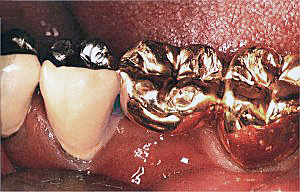

Die Standard - Versorgung stellt einen ausreichenden, wirtschaftlichen und zweckmäßigen Zahnersatz im Sinne der gesetzlichen Krankenkassen dar.

Die Ausführung darf nicht über das notwendige Maß hinausgehen. Dabei können Metalle zur Anwendung kommen, bei denen eine Schadstoffanreicherung in Organen nicht ausgeschlossen werden kann.

Eine zahnfarbende Verblendung der Kronen / Brückenkonstruktion ist nur im Sichtbereich der vorderen Zähne vorgesehen.

Zwar wird im Rahmen einer Standardversorgung die Gebißfunktion wiederhergestellt - ästhetische Erwägungen stehen jedoch leider nicht zur Diskussion.